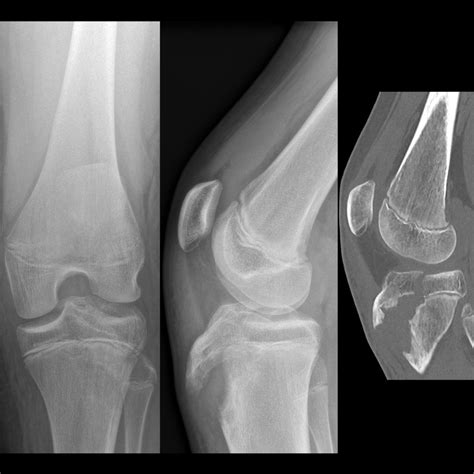

Diagnosing Joint Effusion Knee

Diagnosing joint effusion knee typically involves a combination of physical examination and diagnostic tests. The healthcare provider will:

• Ask about the patient's medical history and symptoms.

• Perform a physical examination of the knee, checking for swelling, tenderness, and range of motion.

• Order diagnostic tests, such as X-rays, MRI, or ultrasound, to visualize the joint and surrounding structures.

• Perform a joint aspiration, where a small amount of fluid is removed from the knee joint using a needle. This fluid can be analyzed to determine the cause of the effusion.